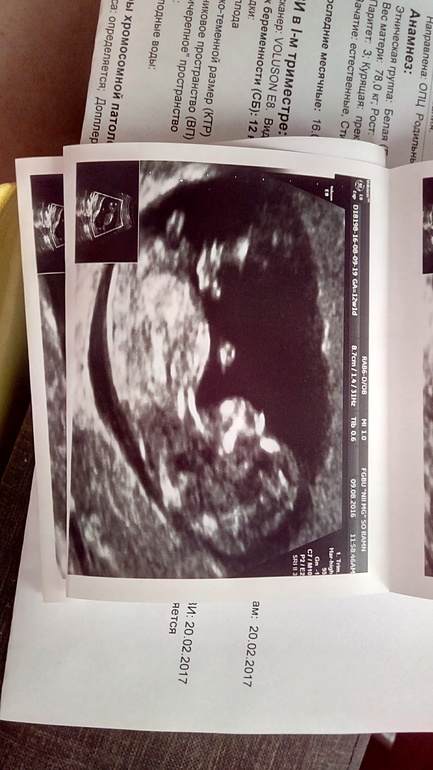

А теперь самое главное...и радостно,и немного тревожно за малыша...Вчера мы прошли первый скрининг в НИИ Генетики. По КТР срок 12 нед. и 1 день,по УЗИ все хорошо,все показатели отличные, а вот по крови...повышен ХГЧ...(((( Уменя такого ни разу не было и,конечно,я расстроилась...((

Ну и наша фоточка!